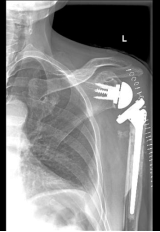

经过充分的术前准备,黄刚主任带队为患者成功实施了左侧反置式人工全肩关节置换手术,手术过程顺利,患者在术后第3天就已经开始左肩关节功能锻炼。患者现在继续接受后期康复治疗,左肩关节功能将有望最大限度的恢复。

反置式人工全肩关节置换术(RTSA)适应用于肩袖骨关节病、肩关节假性麻痹、老年性肱骨头无菌性坏死、类风湿性盂肱关节关节炎、老年患者陈旧性肩关节脱位、盂肱关节骨肿瘤切除术后重建、人工肩关节置换后翻修、肩袖撕裂修补术后失败伴肱骨头持续上移、老年性粉碎性肱骨近端骨折等需要行肩关节置换的病患。由于肩关节功能特殊、解剖结构复杂,术中需在狭窄空间下完成精准截骨,调整后倾角、颈干角、偏心距等,该手术对术者手术技巧要求极高。据了解,2019年广东省该手术病例不超30例。